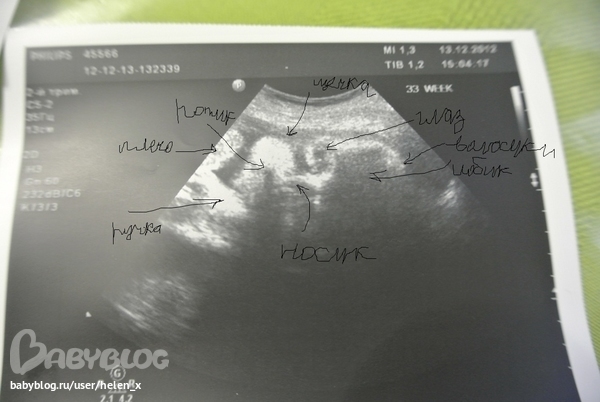

УЗИ 31-32 недельки! Наш малыш - чудо)))

УЗИ, КТГ, доплерПришли с узи, сходили к хорошему врачу, я очень довольна!!! Наш малыш мне показался таким красавчиком, и глазками на нас смотрел, и моргал, и зевал, и жидкость причмокивал. Расстроило то, что крупненький и обвитие пуповиной.

Узистка сказала, что редко когда малыш так поворачивается и смотрит, глазки открывает. На голове уже волосики есть, и вообще головка у нас уже большая - 8,5 см, соответствует 34,3 неделям беременности, длина бедреной кости - 6,3 см, окружность живота - 28,3 см. Положение занял правильное, головкой вниз, ножки прямо под ребрами. Однозначно сыночек, показали яички, правое уже полностью опустилось, левое еще дозревает.

Степень зрелости легких - 2, все внутренние органы в норме и без патологий.

Сердцебиение ритмичное, ЧСС - 148 уд. в мин. За время просмотра отмечались единичные эстриолы.

Доплерометрия ИР в артерии пуповины - 0,55, ИР в маточных артериях - 0,57 и 0,54 (норма до 0,61).

Плацента: степень зрелости - 3. А это значит, что плацента уже устарела, и нужно пить лекарства - например, Актовегин. Количество околоплодных вод нормальное, объем амниотической жидкости - 150. Визуализируется двойной контур пуповины в области шеи плода, с однократным обвитием. Это должно насторожить! Сказала врачу, она сказала, что это ничего страшного, ну не знаю...

Шейка матки - 4,1 см.

Заключение: Плод фетометрически соответствует 33-33,5 неделям беременности. Преждевременное созревание плаценты.

Вес - 2-2,2 кг.